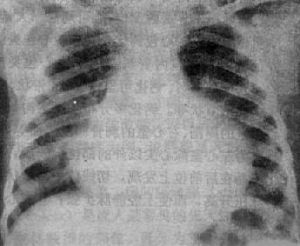

2.X線檢查心包鈣化是曾患過急性心包炎的最可靠的X線徵象,在大多數縮窄性心包炎患者中均可見到,常呈不完整的環狀。心影大小多正常,部分病人輕度增大可能與心包積液或心包增厚有關,部分病人心影呈三角形或球形,心影變直或形成異常心弓,如主動脈結縮小或隱蔽不見,左右心房、右心室或肺動脈圓錐增大,上腔靜脈擴張等。X線透視見心臟搏動減弱或消失,以心包最厚處明顯。還可見肺門影增寬、肺水腫、胸膜增厚或有胸腔積液。